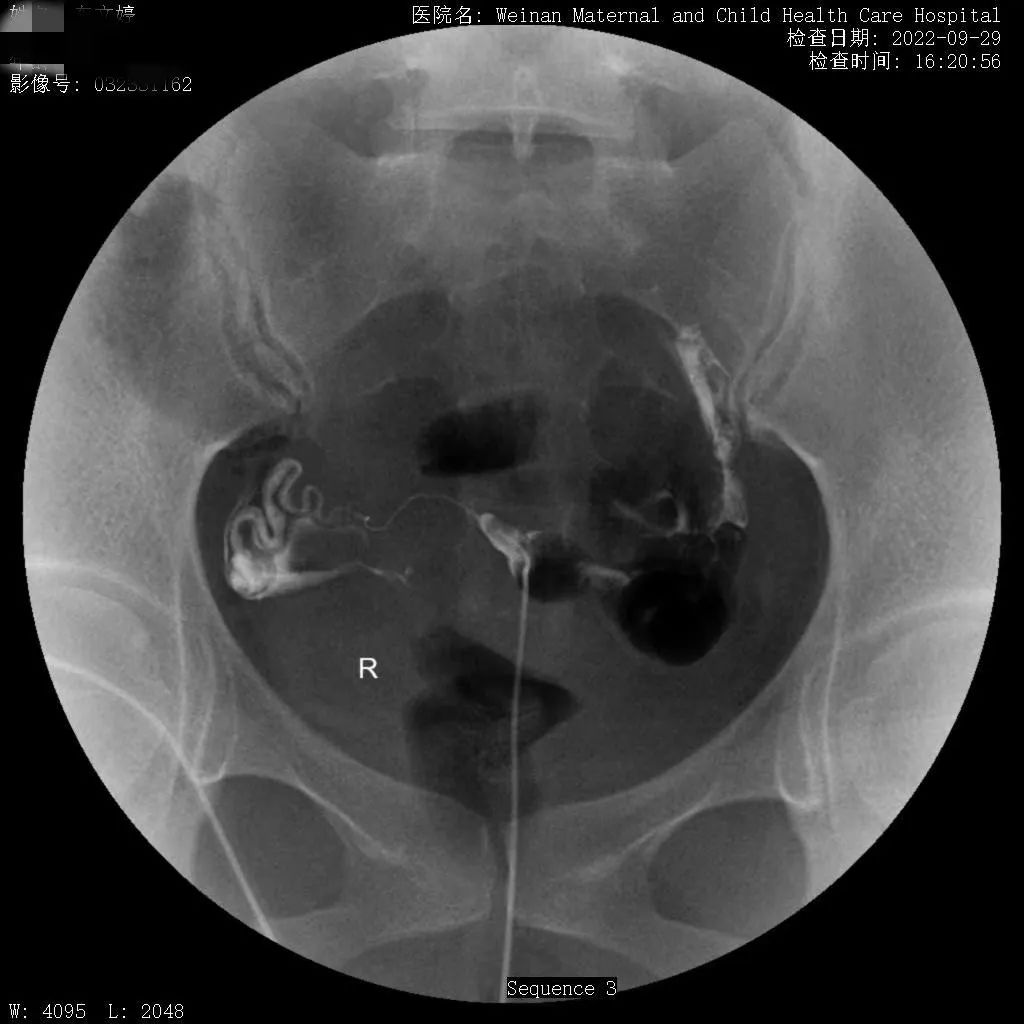

为满足临床需求,除开展传统X线检查外,近年又相继开展了静脉肾盂造影、“T”型管造影及子宫输卵管造影等多种造影检查、乳腺钼靶成像、遥控灌肠治疗小儿肠套叠等较前沿的X线检查。尤其是治疗小儿肠套叠,现已治愈几百余例患儿,遥控灌肠整复仪治疗小儿肠套叠具有安全、迅速、高效的特点,避免了患儿手术,减轻了家庭经济负担。

不育不孕症的子宫输卵管造影检查